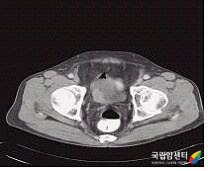

근침윤성 방광암의 전산화단층촬영 사진

[근침윤성 방광암의 전산화단층촬영 사진]